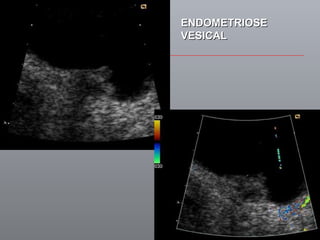

Câncer de Bexiga Estudos de imagens Diagnóstico Ultrassonografia Urografia excretora Estadiamento CT RNM Rx tórax  Cistoscopia + biópsia + biópsias randomizadas

ENDOMETRIOSE VESICAL